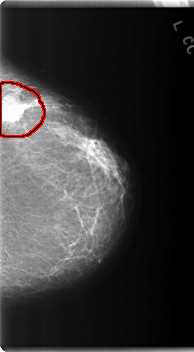

C_0220_1.LEFT_CC

LEFT_CC LINES 5984 PIXELS_PER_LINE 3296 BITS_PER_PIXEL 12 RESOLUTION 50 OVERLAY

FILE: C_0220_1.LEFT_CC.OVERLAY

TOTAL_ABNORMALITIES 1

ABNORMALITY 1

LESION_TYPE CALCIFICATION TYPE AMORPHOUS DISTRIBUTION CLUSTERED

LESION_TYPE MASS SHAPE IRREGULAR MARGINS SPICULATED

ASSESSMENT 5

SUBTLETY 5

PATHOLOGY MALIGNANT

TOTAL_OUTLINES 1

BOUNDARY